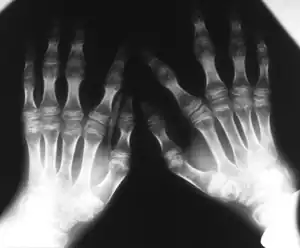

| Kniest dysplasia- Hands demonstrate flattening of metacarpal epiphyses, carpus has a disorganized aspect | |

The images taken will help to identify any bone anomalies. Two key features to look for in a patient with Kniest dysplasia is the presence of dumb-bell shaped femur bones and coronal clefts in the vertebrae. Other features to look for include:

- Abnormal growth of epiphyses, metaphyses, and diaphysis

- Short tubular bones

- Narrowed joint spaces